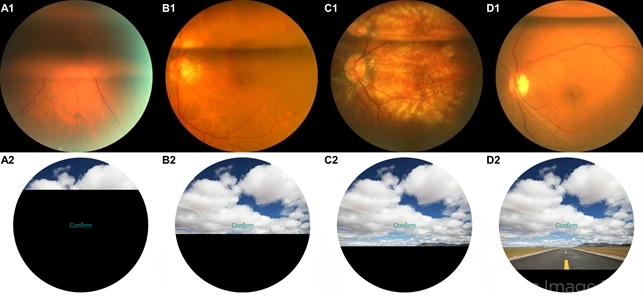

JPM Free Full Text Pneumatic Retinopexy Involving The Use Of

JPM Free Full Text Pneumatic Retinopexy Involving The Use Of